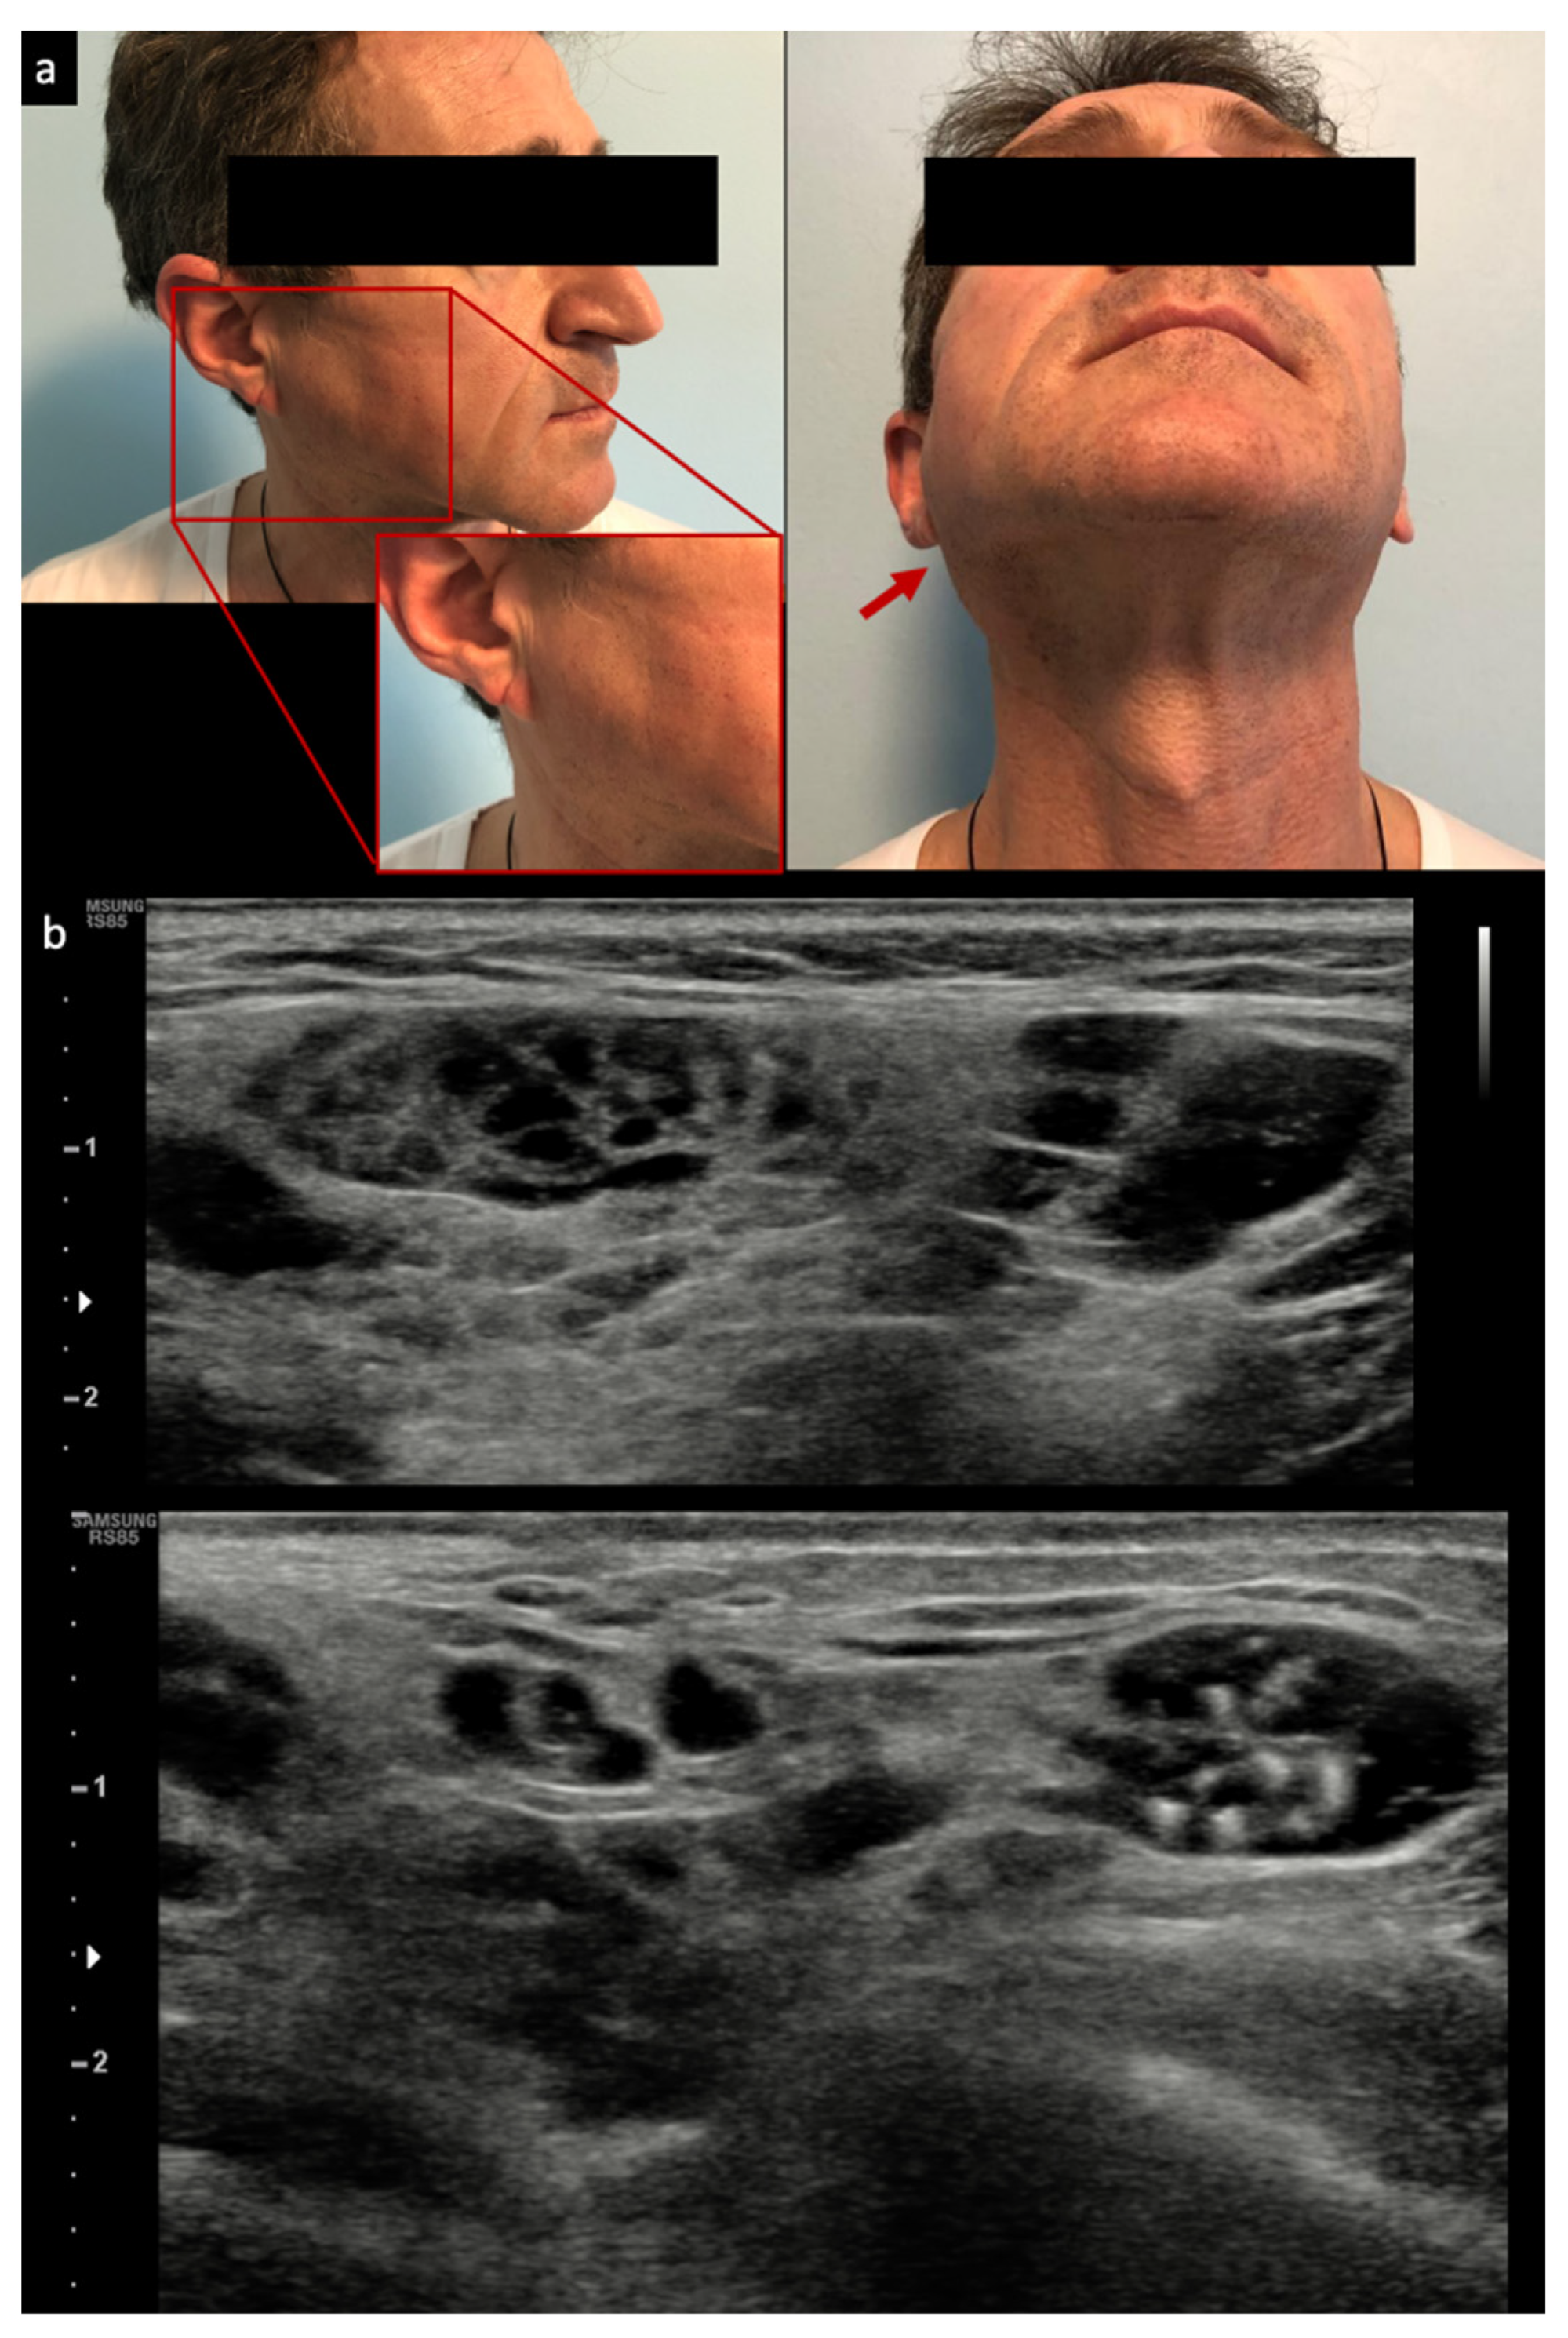

- Zabotti, A.; Zandonella Callegher, S.; Lorenzon, M.; Pegolo, E.; A Scott, C.; Tel, A.; Giovannini, I.; Robiony, M.; Di Loreto, C.; Zuiani, C.; et al. Ultrasound-guided core needle biopsy compared with open biopsy: A new diagnostic approach to salivary gland enlargement in Sjögren’s syndrome? Rheumatology 2021, 60, 1282–1290. [Google Scholar] [CrossRef]